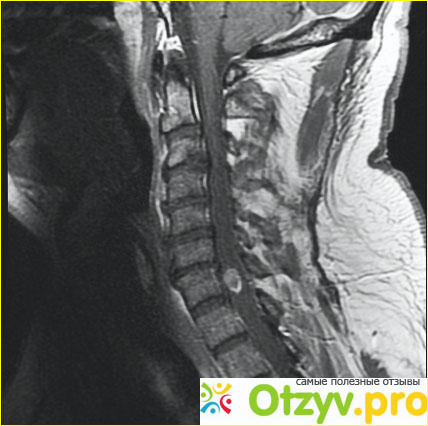

Обычно метастазы, которые проникают в кости, являются следствием развития рака. Многие виды рака дают такие метастазы. Это и рак молочной железы, и рак легкого. Может такое произойти и в результате рака щитовидной железы. К сожалению, список этим не заканчивается. Метастазируют рак почек и лимфомы. Вероятность получить метастазы в позвоночнике разная, зависит от вида и степени рака. Так, рак предстательной и молочной желез развивает 80% метастазов. Следует отметить, что первичные опухоли костей встречаются гораздо реже метастазов. Обычный путь метастазов – гематогенный. Встречается также и непосредственное прорастание опухоли в самой кости. Если говорить о частоте поражения костей, то можно выделить поражение позвонков и бедренных костей. Они поражаются чаще других костей. За ними следуют кости таза , ребра, а затем грудины. Немного реже страдают отделы плечевой кости и кости черепа.

Самый эффективный метод выявления метастазов – проведение ренгенографии. Недостатком этого метода является то, что метастазы маленьких размеров, меньше 1 см, выявить очень сложно. А чаще они просто не видны. Остеолиз зачастую сопровождается гиперкальцемией.

Больше надежды обнаружить остеопластические метастазы при помощи сцинтиграфии. Если провести рентгенографию, на пленке можно будет увидеть повышенную уплотненность кости, также возможен вариант обнаружения очагов остеосклероза. Остеогенез почти всегда развивается на фоне повышенной активности ЩФ.